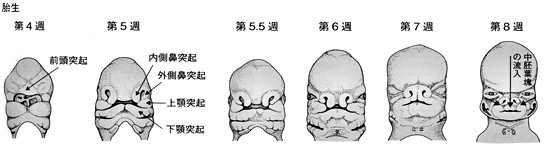

口唇は胎生8週頃に、口蓋は胎生12週頃にできあがります。口唇や上顎、口蓋を形成するための突起といわれる組織が、それぞれ上方や側方から伸びてきて、顔面や口蓋の中央部で癒合することで、口唇や口蓋が形作られます。この癒合過程が、なんらかの原因で障害された時に口唇裂、口蓋裂が生じます。口唇裂や口蓋裂は、別々に起こることもありますが、同時に見られることが多いです(図1)。

(白砂兼光、古郷幹彦:口腔外科学第3版、顔面・口腔の異常、医歯薬出版、東京、2011より)